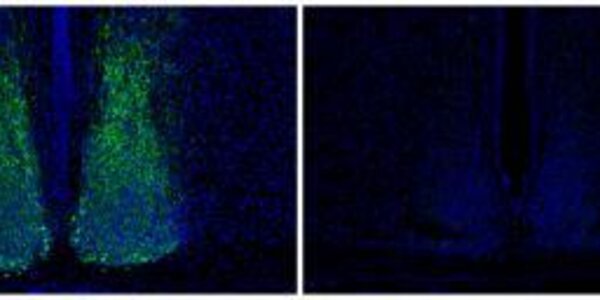

Notch Signaling And New Blood: Tracing The Beginnings Of Hematopoietic Stem Cells

Hematopoietic stem cells (HSCs) are adult stem cells isolated from blood or bone marrow that can renew themselves and differentiate into a variety of specialized cells. They give rise to all other blood cell types but their development has long remained a mystery. In a new paper, researchers elaborate upon a crucial signaling pathway and the role of key proteins, which may help clear the way to generate HSCs from human pluripotent precursors, similar to advances with other kinds of tissue stem cells.   Principal investigator David Traver, PhD, professorat U.C. San Diego School of…